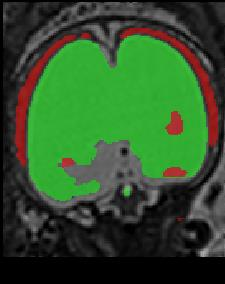

Limiting failures of machine learning systems is of paramount importance for safety-critical applications. In order to improve the robustness of machine learning systems, Distributionally Robust Optimization (DRO) has been proposed as a generalization of Empirical Risk Minimization (ERM). However, its use in deep learning has been severely restricted due to the relative inefficiency of the optimizers available for DRO in comparison to the wide-spread variants of Stochastic Gradient Descent (SGD) optimizers for ERM. We propose SGD with hardness weighted sampling, a principled and efficient optimization method for DRO in machine learning that is particularly suited in the context of deep learning. Similar to a hard example mining strategy in practice, the proposed algorithm is straightforward to implement and computationally as efficient as SGD-based optimizers used for deep learning, requiring minimal overhead computation. In contrast to typical ad hoc hard mining approaches, we prove the convergence of our DRO algorithm for over-parameterized deep learning networks with ReLU activation and a finite number of layers and parameters. Our experiments on fetal brain 3D MRI segmentation and brain tumor segmentation in MRI demonstrate the feasibility and the usefulness of our approach. Using our hardness weighted sampling for training a state-of-the-art deep learning pipeline leads to improved robustness to anatomical variabilities in automatic fetal brain 3D MRI segmentation using deep learning and to improved robustness to the image protocol variations in brain tumor segmentation. Our code is available at https://github.com/LucasFidon/HardnessWeightedSampler.